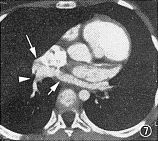

6例行心血管造影但未手术患者,均为完全型肺静脉异位连接,其中心上型5例,心脏型1例(图7~9)。2例合并房间隔缺损,4例合并单心室、右室双出口、肺动脉闭锁等复杂畸形(表1)。心血管造影未提出肺静脉引流异常者2例,其中心上型及心脏型各1例。尚有1例心上型肺静脉异位连接,心血管造影诊断为部分型。

图7,8 完全型肺静脉异位连接(心脏型),为同一病例。图7示右肺静脉(白三角),与左肺静脉(短箭头)合成一共同静脉干(长箭头)引流入右心房。图8示左肺静脉(箭头)经共同静脉干引流入右心房